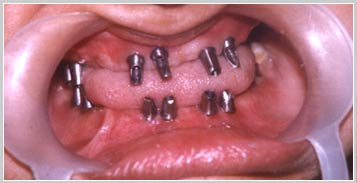

Full Mouth Implants (Case1 : 42 yr female)

This 42 yr female patient reported with grossly carious and mobile teeth needing extraction . After removal of all the teeth 8 implants were inserted in upper jaw and 8 in the lower jaw in two surgeries one week apart.

Patient was given temporary Dentures . After 4 months, full mouth bridges were given on the implants.

The implant supported bridges are in service for 5 years now.